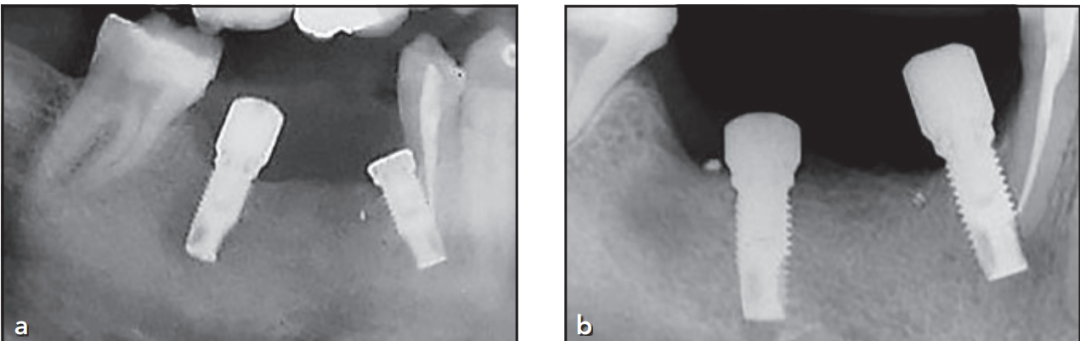

尽管下颌神经上方骨高度充足(图1a),但因张口受限及术野暴露困难,仅能植入短种植体(10 mm);

备洞时钻针远中向倾斜过度,导致第一前磨牙根尖区牙髓神经断裂(图1b)。

(a) 术前X线片评估

术前影像显示:

下颌右侧第二前磨牙及第一磨牙缺失区可见骨碎片残留;

下颌神经管位置明确,上方骨高度充足。

(b) 术后X线片表现

术后影像证实:

两枚种植体就位良好,骨结合界面清晰;

第一前磨牙根尖区可见神经横断征象,系备洞时钻针远中向偏移所致。